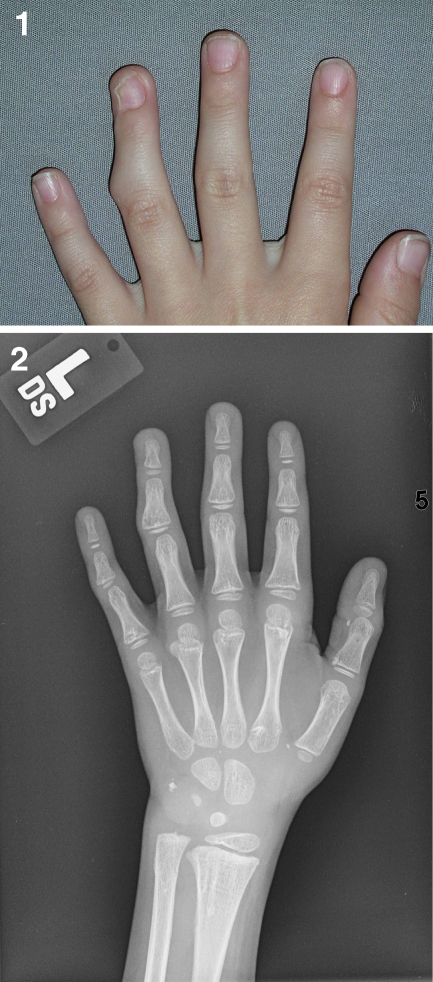

A younger sibling of patient #1 was born 4 years later. She was the younger of two fraternal twins (one boy and one girl). She also has multiple exostoses in the hands and the feet. The sister presented at 24 months of age with a 4-month history of finger nodules. Physical examination showed palpable nodules on the radial dorsal aspect of the right index finger at the DIP joint and at the ulnar palmar aspect of the right long finger at the distal proximal phalanx. A radiograph (Fig. 6) shows that there is no stalk between the nodule and the right index finger similar to the case of her elder brother. Currently, she has no deviation of the fingers, appears not to be symptomatic, and has no functional problems. She has not had surgery and she will be followed routinely.

Fig. 6.

A radiograph (patient #2) shows two exostoses on the right hand, one at the index finger DIP joint, which does not have a stalk to the phalanx, and the other on the long finger at the distal proximal phalanx

Patient #3

The third patient is the father of patient #1 and patient #2. He is older by 30 years than patient #1. He is the first person in his family to present with multiple exostoses. His nodules were identified early when he was very young. He did not undergo surgery though until he was 6 years old. Six exostoses were removed: one from the right ring finger at the palmar side of the PIP joint, a second from the right middle finger at the dorsal side of the MP joint, a third from the right index finger at the web space, a fourth from the left middle finger at the palmar MP joint, a fifth and a sixth from the right and left index finger at the dorsal aspect of the DIP and the MP joint, respectively. He has since been asymptomatic since his surgery and has no functional problems (Fig. 7).

Fig. 7.

Thirty-one years after the operation, patient #3 does not present either recurrence or functional deformity